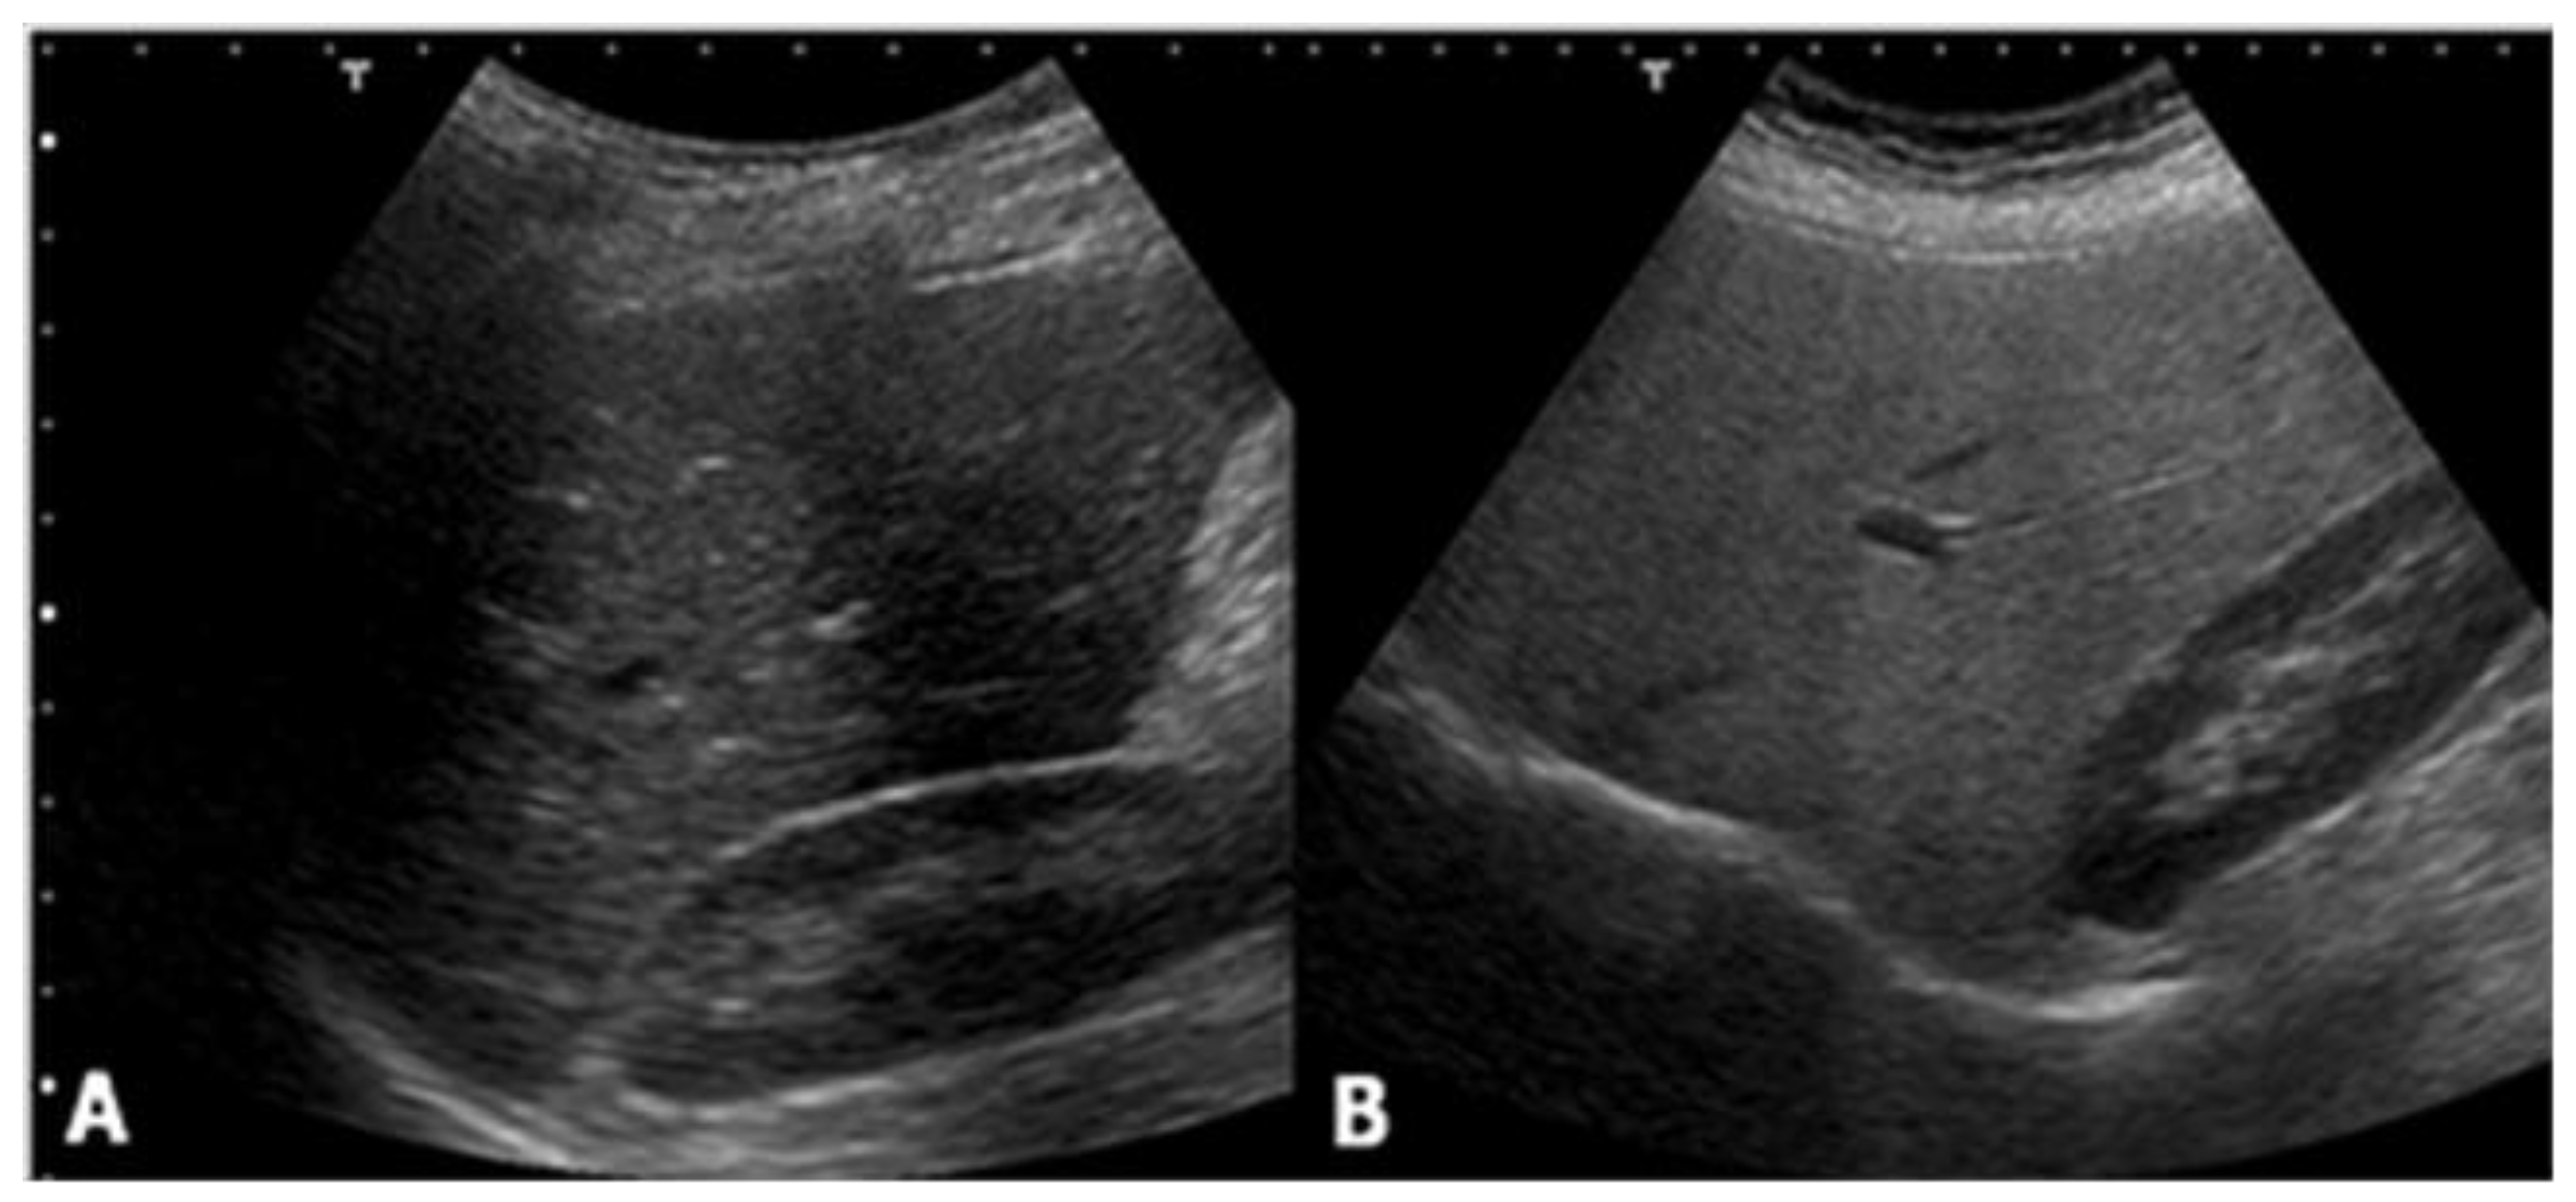

Ultrasound is the most common imaging technique used for the evaluation of liver steatosis. Due to its significant advantages, such as being largely available, relatively non-expensive, and easy to use, ultrasound has been adopted as the standard care for the screening of a patient suspected of having NAFLD. Healthy liver parenchyma shows homogeneous echo texture and similar echogenicity compared to the right kidney cortex. However, in hepatic steatosis, the presence of lipid droplets within hepatocytes disturbs the propagation of the sound wave, causing scatter and attenuation. As waves scatter, more echoes return to the ultrasound transducer. This increase in signal from the liver produces a brighter visualization of liver parenchyma, compared to the kidney. Attenuation of the ultrasound waves also causes depth-dependent loss of signal, leading to an obscuration of vessels and bile ducts, and blurring of the diaphragm (Figure 1).

Figure 1.

Ultrasound shows no difference between (A) the liver and right kidney cortex echogenicity, while (B) it demonstrates a hyperechoic liver compared with the kidney parenchyma.